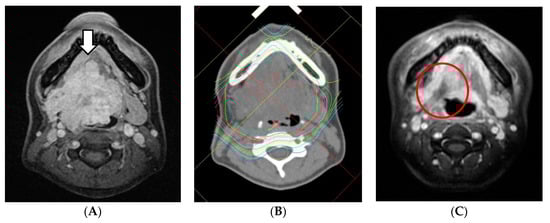

2.4. Toxicities

With regard to acute toxicities, those higher than grade 3 were as follows: oral mucositis in 12 patients (80%), dermatitis in three patients (20%), neutropenia in two patients (13%), and anemia in one patient (7%). Separately, grades 1 or 2 pharyngeal mucositis (ulcer) occurred in four patients within 2 months from the end of the treatment (Figure 3). With regard to late toxicities, grade 4 dysphagia and grade 5 pharyngeal necrosis were observed in one patient. No cases of irreversible dry mouth or mandibular osteomyelitis occurred (Table 4).

Pharyngeal ulcers sometimes occur after radiation therapy, and pharyngeal necrosis as a late disorder can be fatal. Previously, after treatment using CIT for ACC of the base of the tongue, in three of 18 cases (21%), a necrotic ulcer was reported but the ulceration and pain disappeared with tumor regression [17]. In this study, three cases of grade 2 ulcer formation and two cases of grade 3 ulcer formation occurred. The first treatment case developed grade 4 dysphagia and grade 5 pharyngeal necrosis due to delayed conservative treatment. This is because it was not possible to judge whether the ulcer that appeared in the base of the tongue was due to residual tumor or tissue necrosis. Since then, conservative treatment has been performed with great care, and thereafter all cases were cured.

Figure 3. MRI of a patient, cT4aN0M1 (lung), before and after treatment. The tumor showed a CR but necrotic ulcer occurred. It was healed with conservative treatment. (A) Before treatment. White arrow: tumor. (B) The dose distribution of PBT. (C) After 2 months. Red circle: necrotic ulcer.